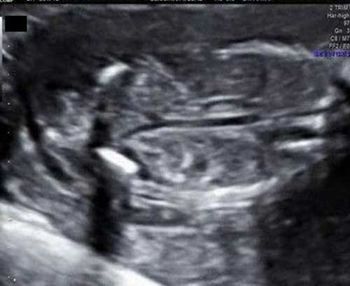

Do these images of the fetal brain point to a congenital anomaly or something else?

This second-trimester fetus has a renal abnormality. Can you identify it?